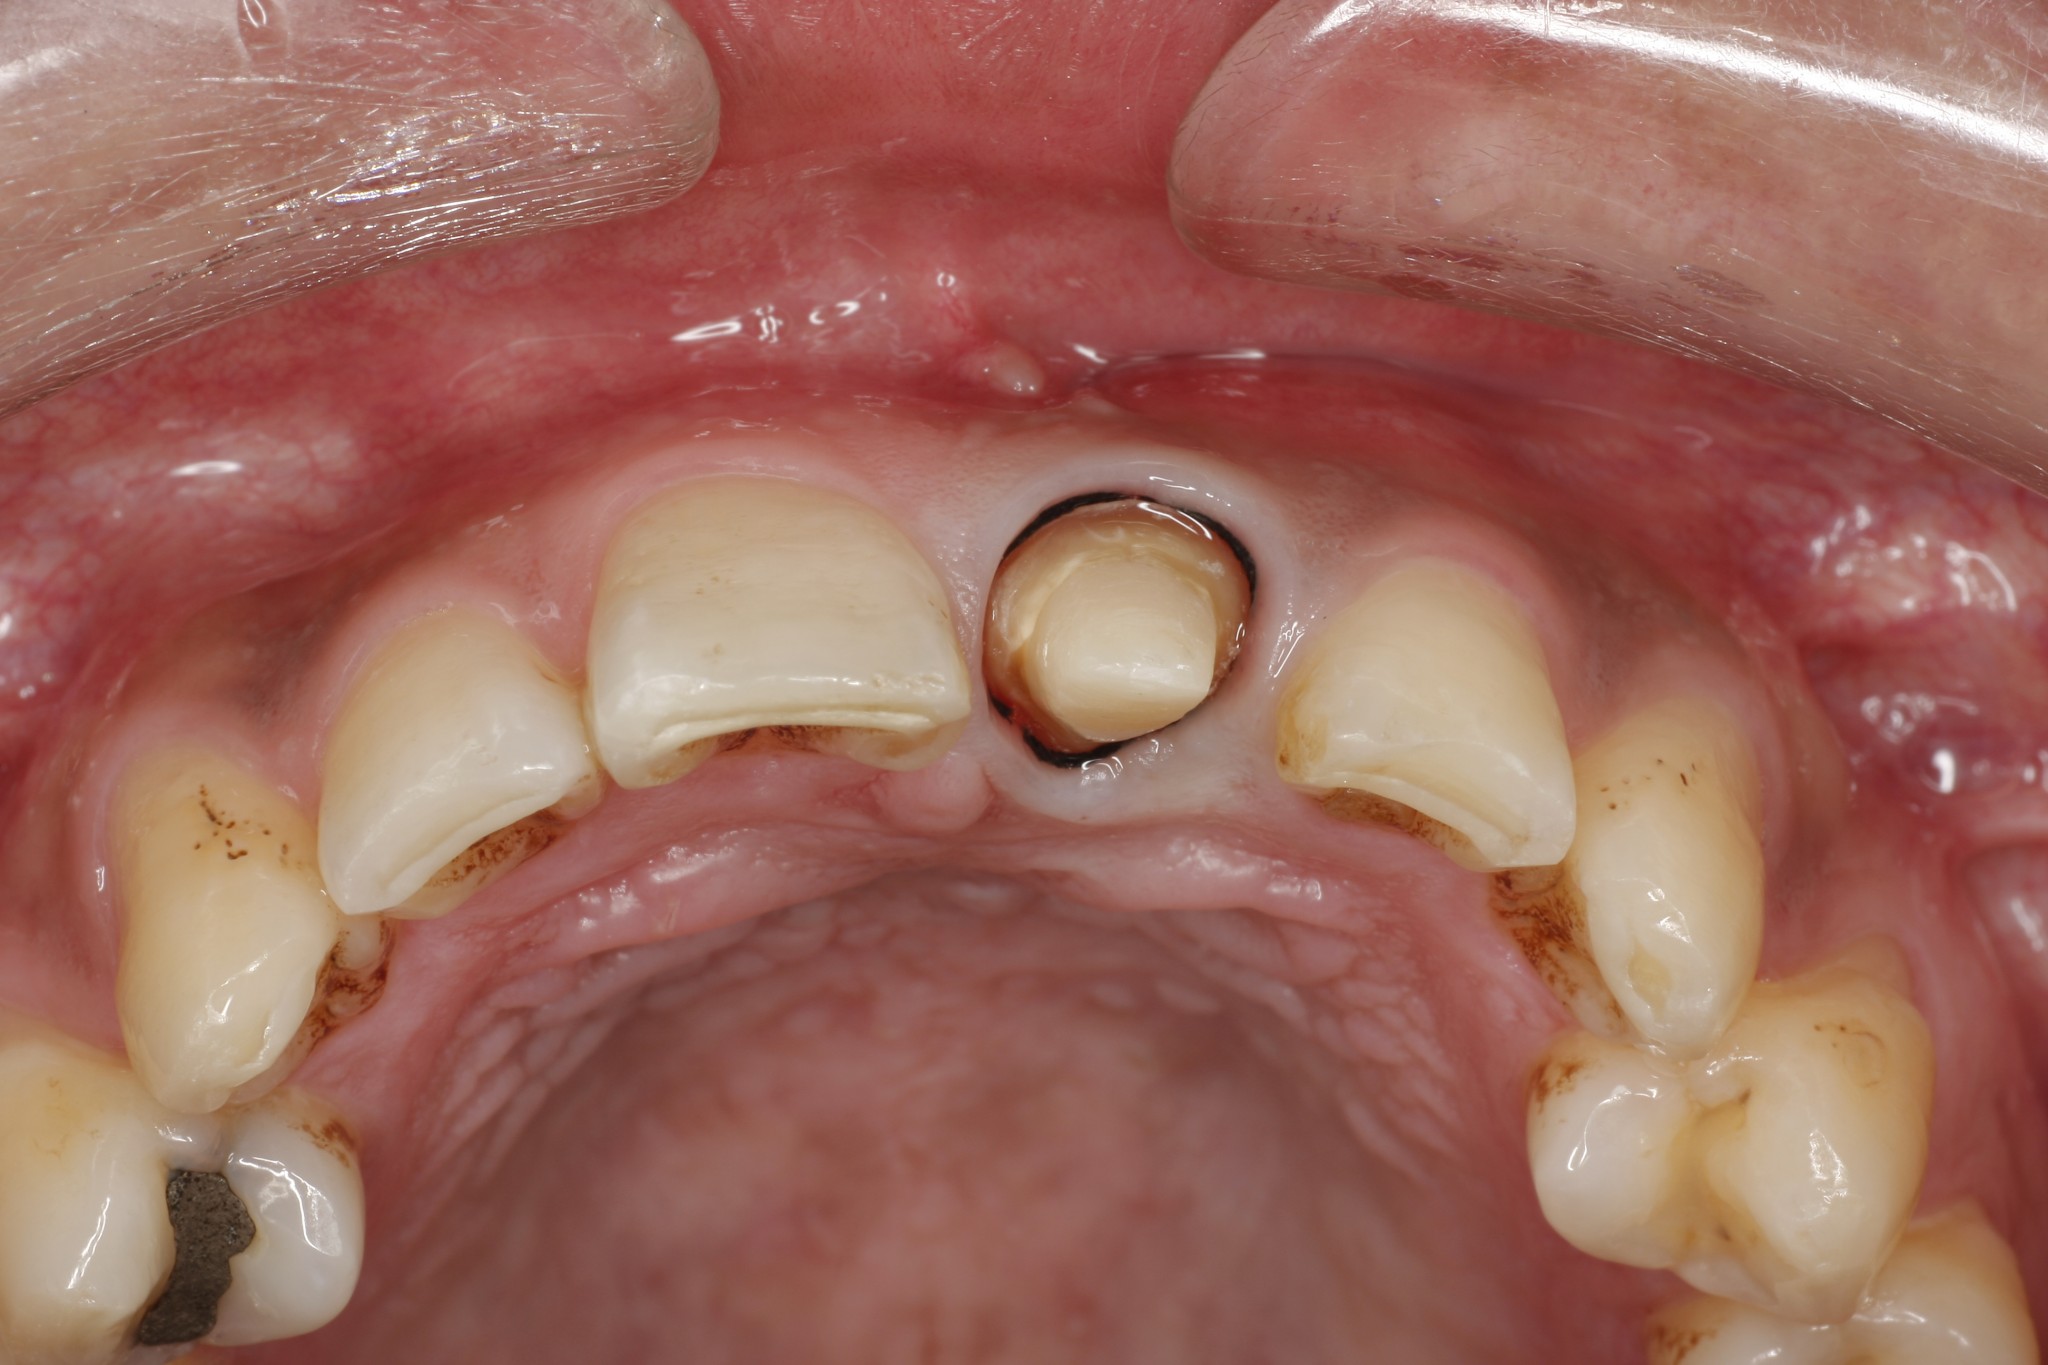

治療症例集 佐伯歯科クリニック 福岡市早良区 西新近くの 予防型 歯医者 歯科 荒江

前歯6歯の審美歯科 症例紹介 宮本歯科

全身の健康と歯科治療 かみ合わせ セラミック治療例 30代女性 126 東京赤坂ヴィーナスデンタル